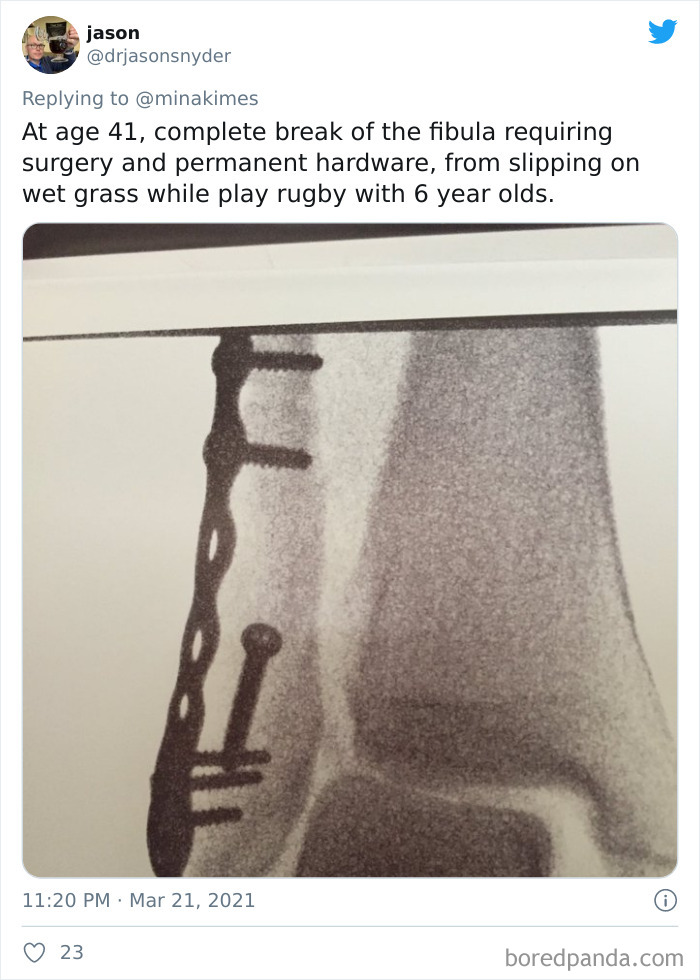

As we age, our bodies tend to get weaker. Our bones shrink in size and density, our muscles lose strength and flexibility, and we become more prone to accidents. However, getting into the habit of moving lots and being physically active is one of the ways that we can offset the gradual decline of our bodies.

Activities like walking, swimming, weight training, and calisthenics help us stay strong, less prone to injury, and keep our bodies fit, so we recover from accidents quicker than if we were couch potatoes.